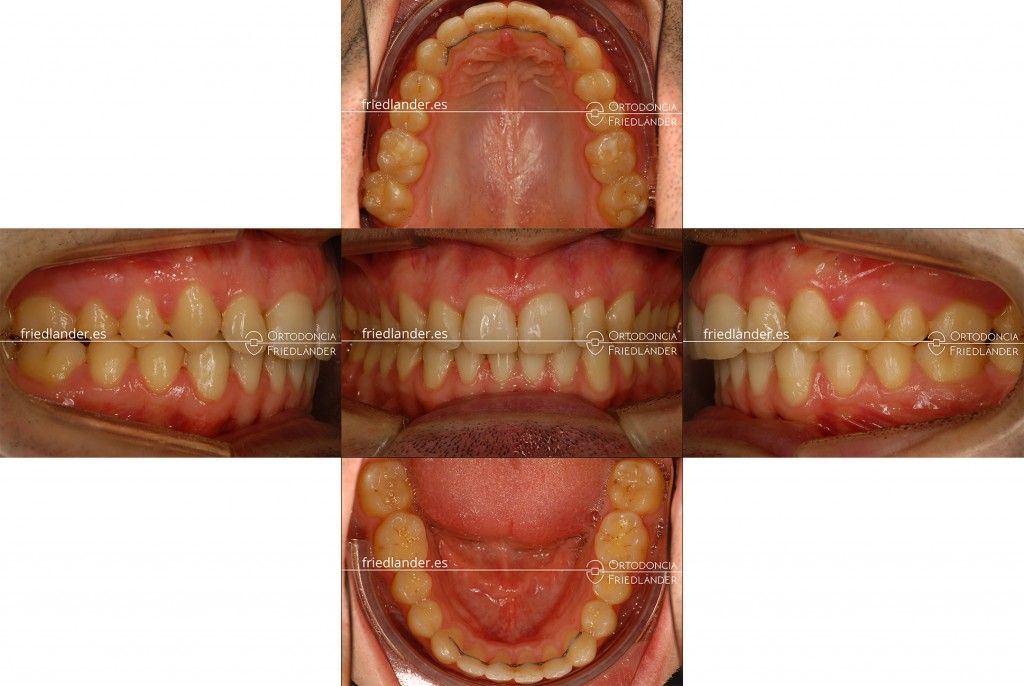

Al cabo de 22 meses de tratamiento hemos conseguido una correcta clase I y el paciente estaba muy contento con los resultados.

Imagen del frente anterior y de boca abierta comparando el antes y el después.